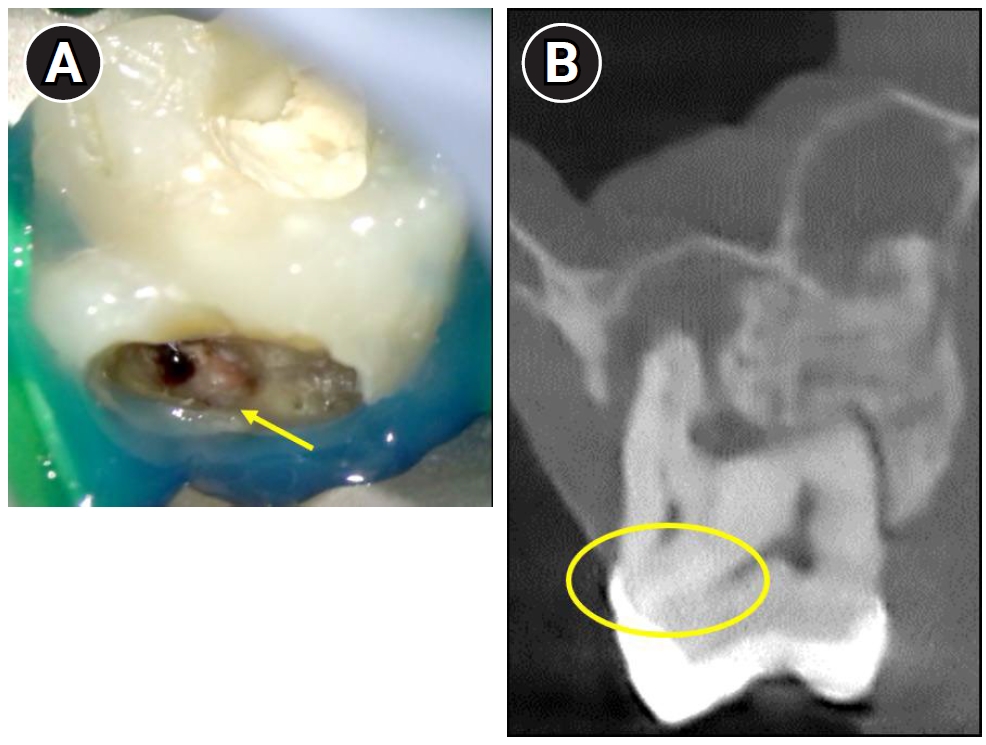

A 17-year-old male patient presented with a chief complaint of noticing a lesion on the gingiva without experiencing any associated pain (Figure 1A). Clinical examination revealed a sinus tract on the palatal gingiva of the maxillary right first molar (#16) (Figure 1B). The tooth exhibited pain to palpation, while percussion and mobility tests were normal.

Difficulty in identifying the palatal canal due to the presence of a localized cervical mineralized diaphragm (CMD) near the palatal region. (A) Clinical view showing a mineralized barrier (yellow arrow) obstructing access to the palatal canal. (B) Cone-beam computed tomography image revealing CMD in the palatal area (highlighted with a yellow circle).